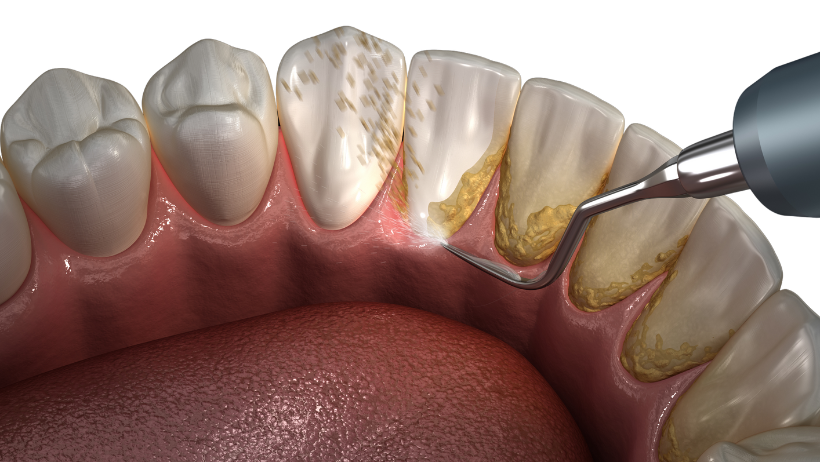

Gingivitis je površinska upala zubnog mesa bez utjecaja na potpornu kost. Uzrokuje ga najčešće neadekvatna oralna higijena te nakupljanje dentobakterijskog plaka koji mineralizira u zubni kamenac. Najčešći simptomi su otečene desni koje krvare.

Stoga se preporučuje čišćenje zubnog kamenca najmanje 1-2 puta godišnje, a kod nekih pacijenata i češće, ovisno o stanju parodonta.

Terapijski postupci uključuju mehaničko čišćenje – struganje i poliranje korijena zuba kako bi se uklonio plak i kamenac (inicijalnu terapiju) te po potrebi kirurške zahvate.